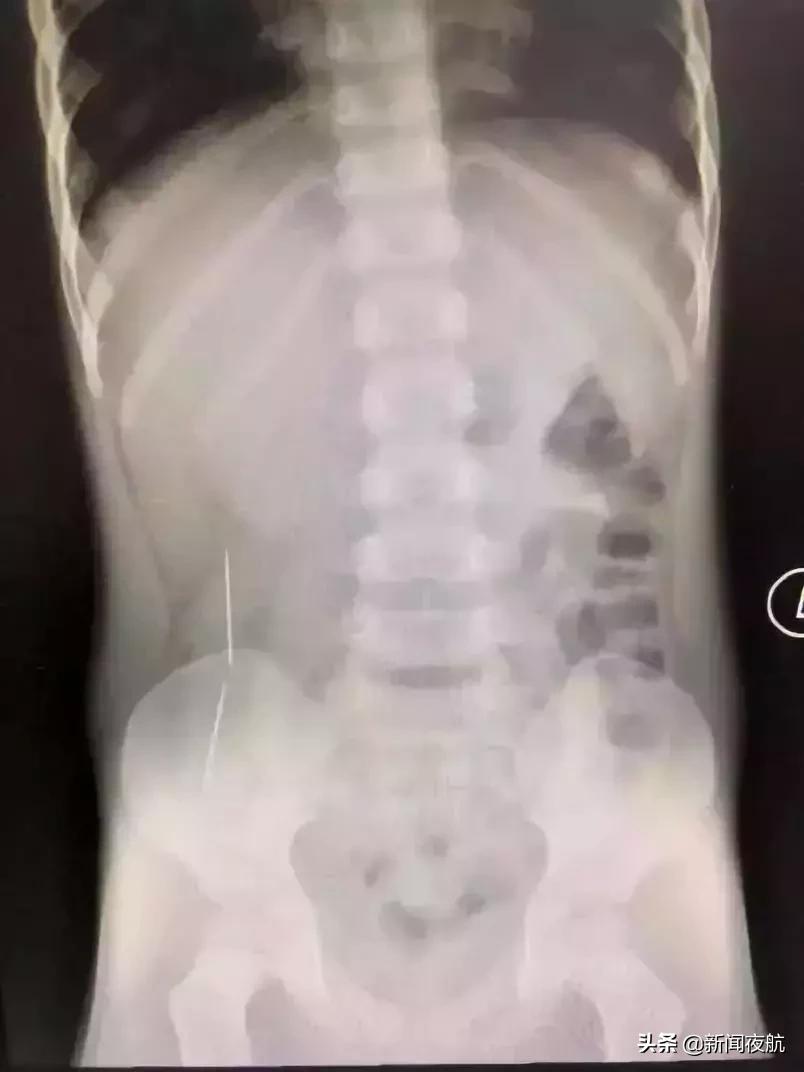

深圳市儿童医院还曾接诊了一位误吞了两条绣花针的小孩彬彬。彬彬妈妈说,他原本是吃了三根针,有一根因为呛咳当时吐了出来,剩下的两条针就全部吃了进去。

当时,看到X光片,在场所有的人都倒吸一口凉气。而且这两条已在彬彬肠胃穿游数日的绣花针,已穿透了他的肠管造成穿孔,他的腹腔内已造成了感染。情况十分不妙。好在手术及时,没有造成大量粪便外渗,孩子转危为安。